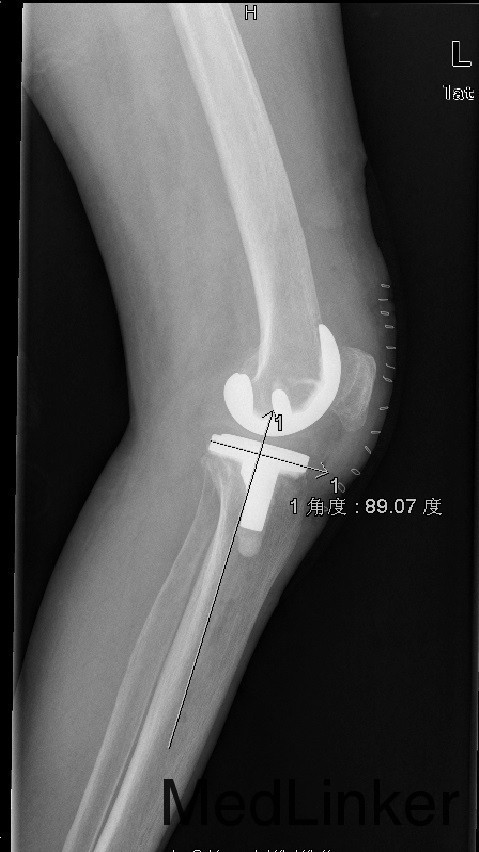

诊断:1、左膝骨关节炎伴屈曲畸形 2、左髌骨骨折骨愈合 治疗:积极行术前准备后于全麻下行左侧全膝关节置换术+软组织松解术,术后常规治疗。

患者术后功能良好,症状缓解,生活治疗提高 1、股骨外翻截骨如何在X线片上定角度?